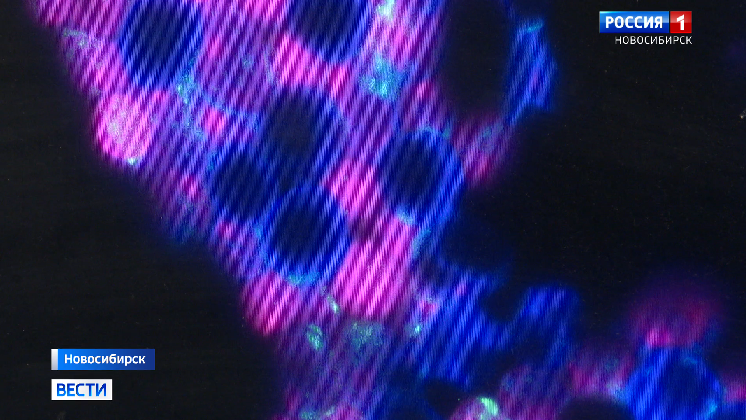

Находка оказалась случайной. Во время рутинной работы ученые изучали грибы. Одна из сотрудниц перепутала праймеры - это такие пробирки с прозрачной жидкостью внутри. Провела исследование и как оказалось - нашла бактерии , которые там и быть не должны.

Рассматривали тогда внутренние органы кур. Чтобы разобраться в причинах трех вспышек заболеваний на сибирских птицефабриках. Пернатые гибли. Лекарства не помогали. Вскрытие показало - в организмах куриц бактерии соседствуют с грибком. К животным и человеку он часто попадает вместе с пищей.